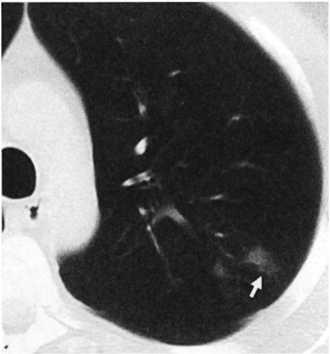

Основной рентгенологический признак очагового туберкулеза — очаговая тень, т.е. затемнение диаметром не более 1,2 см. Самые ранние проявления свежего очагового туберкулеза легких могут быть обнаружены при КТ (рис. 10.3). Более поздние очаговые изменения можно рассмотреть при стандартной рентгено- или флюорографии. На снимке обычно видна небольшая группа очаговых теней малой интенсивности, округлой формы, с нечеткими контурами. Размеры теней преимущественно средние и крупные — от 4 до 12 мм. Заметна тенденция к их слиянию. Очаги, имеющие такое отображение на рентгенограмме, нередко называют мягкими (рис. 10.4). При КТ можно уточнить характер поражения — определить уплотнение ткани вокруг очагов, визуализировать просвет пораженного туберкулезным воспалением бронха (рис. 10.5). Иногда в очаге обнаруживают полость распада (рис. 10.6). При продуктивной тканевой реакции очаги приобретают среднюю интенсивность, более четкие контуры, их размеры уменьшаются до 3—6 мм (рис. 10.7). Очаговые тени хорошо отграничены от окружающей ткани и не имеют тенденции к слиянию (рис. 10.8, 10.9).

ris10 3

Рис. 10.3. Начальная стадия очага Абрикосова. Стрелка указывает на очаги Абрикосова. КТ